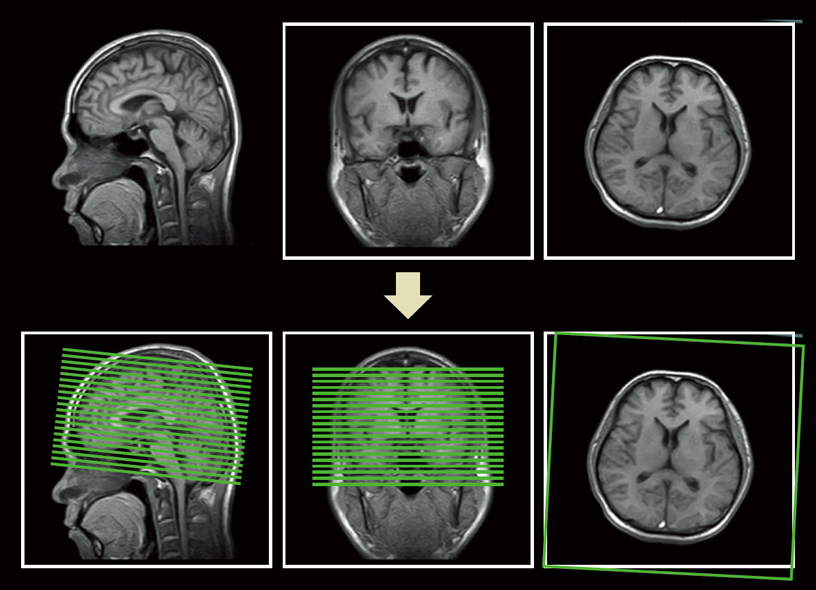

AutoPose is a function that supports slice line parameters. This function allows faster set-up of the OM or AC-PC lines used in head examinations and reduces strain on the operator. Prior settings such as teach/register and 3D data acquisition are not required.